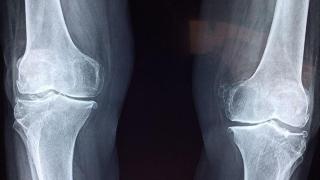

Lo más habitual es que la enfermedad afecte a las articulaciones del dedo gordo del pie, la rodilla o el tobillo. De hecho, la primera aparición suele hacerla en esta primera zona, cuenta Nieto. El reumatólogo explica que la enfermedad aparece en forma de brotes que, con el paso del tiempo, se van haciendo cada vez más frecuentes.